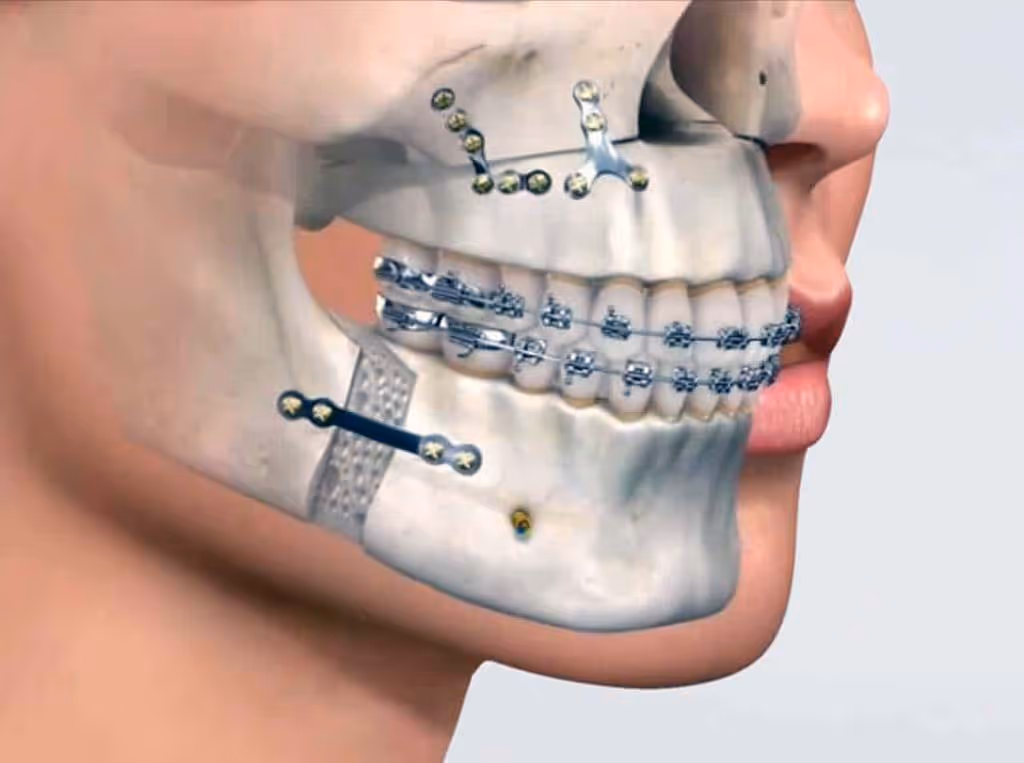

Existen determinados casos en los que la diferencia entre la posición de los maxilares (maxilar superior y mandíbula) es tan grande que un tratamiento de ortodoncia convencional no será suficiente para corregir la mordida.

En estos casos se realizan tratamientos combinados de ortodoncia y cirugía ortognática.

Realización de la cirugía ortognática